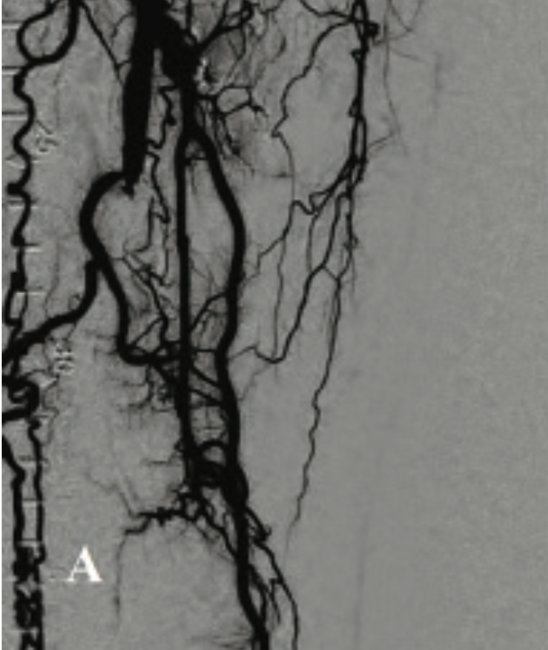

Treatment of Totally Occluded Popliteal Artery With the Auryon Laser Via Pedal Access in a Patient With Chronic Limb-Threatening Ischemia